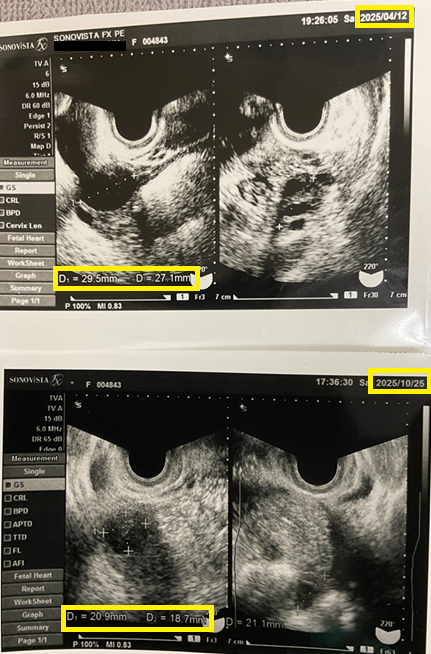

症例報告:卵巣嚢腫74mm→20mmへ縮小した症例

その後、約3年間の経過の中で 卵巣嚢腫の縮小が確認され、2025年10月に寛解となりました。

【右卵巣嚢腫サイズの経過】